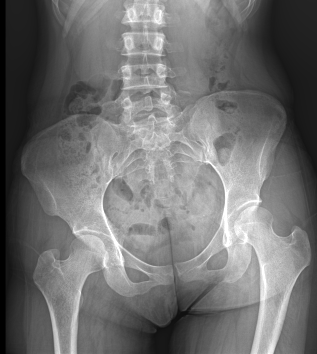

전신 엑스레이·근막 테스트로 짧아진 근육, 과긴장 부위, 기능 저하 부위를 확인합니다.